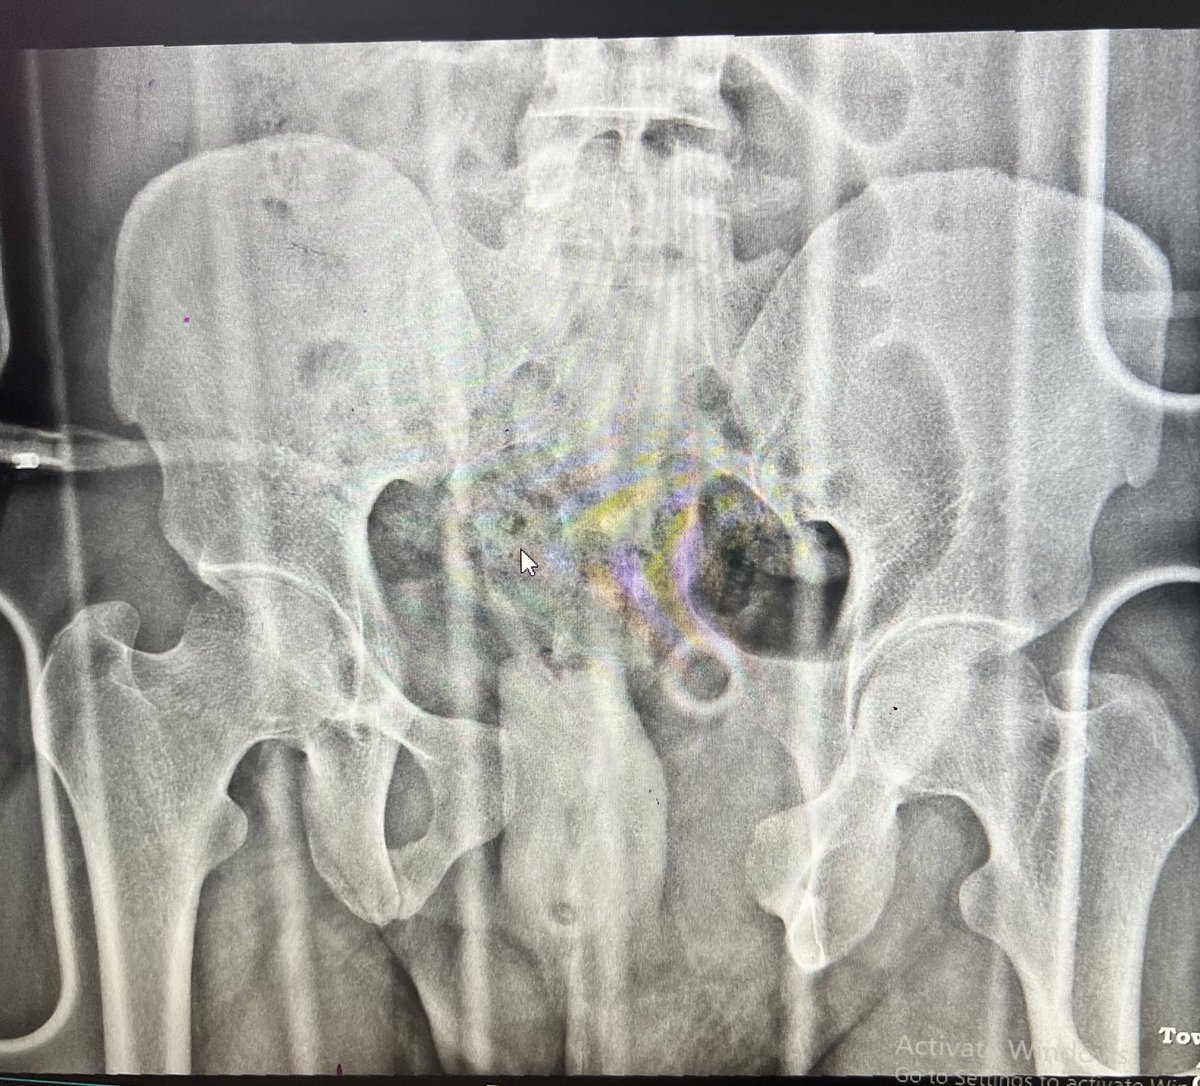

24 m, RTA, has SIJ, diastasis and bilateral pubic rami fractures. After fixing SI Joints, how would you manage the antr ring injury?

Pfannensteil and plate the symphysis? AIP and go supr to both fractures?

Infix?

Would like to hear your thoughts #orthotwitter

@centerofhip @JaiRawal12 I’d plate the symphysis and put screws in the rami/AC bilaterally. Assuming there is no bladder injury.